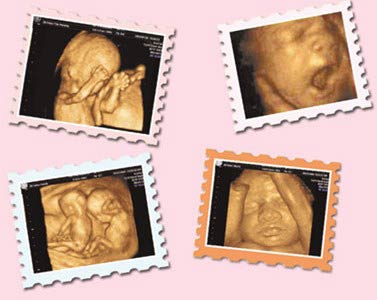

西安安琪兒婦產(chǎn)醫(yī)院引進動態(tài)彩超系統(tǒng)(4D),能夠清晰顯示出未出生寶寶的即時動態(tài)活動圖像,可以將寶寶的樣子和動作制作成照片或影響光盤,讓他擁有更完整的零歲相冊,給父母及今后的孩子留下珍貴的紀念。更為重要的是,四維彩超能夠全方位、多角度的觀察宮內(nèi)胎兒的生長發(fā)育情況,為早期診斷胎兒先天性體表畸形和先天性心臟疾病提供了準確全面的科學依據(jù)。

5.深刻意義:通過四維彩超,準媽媽可以清楚的看到寶寶的模樣和寶寶的動作,為寶寶制作“零”歲相冊,甚至可以刻錄成光盤,有重大的紀念意義。